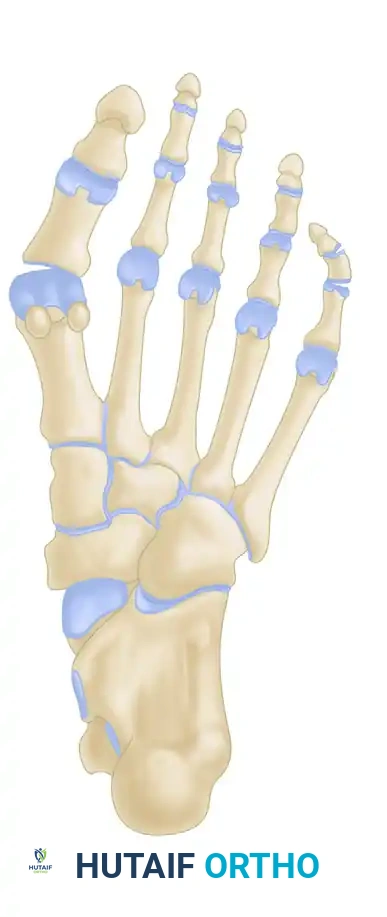

Radiographic Evaluation

Standard weight-bearing anteroposterior (AP), lateral, and oblique radiographs of the foot are mandatory for the accurate assessment of a bunionette deformity. The AP radiograph is utilized to measure several critical angles that dictate surgical decision-making.

Key Radiographic Parameters

- 4-5 Intermetatarsal Angle (IMA): Formed by the intersection of the longitudinal axes of the fourth and fifth metatarsals.

- Normal: Less than 8 degrees.

- Pathologic: Greater than 8 degrees indicates pathological divergence of the fifth ray.

- Fifth Metatarsophalangeal (MTP-5) Angle: Formed by the longitudinal axis of the fifth metatarsal and the longitudinal axis of the proximal phalanx of the fifth toe.

- Pathologic: Usually greater than 14 degrees in symptomatic patients.

FIGURE 83-40 Measurement of metatarsophalangeal-5 and 4-5 intermetatarsal angles for evaluation of bunionette deformity.

- Lateral Deviation Angle (LDA): This angle evaluates the intrinsic bowing of the fifth metatarsal shaft. It is formed by a line bisecting the metatarsal head and neck intersecting with a line drawn parallel to the medial cortex of the proximal fifth metatarsal shaft.

- Normal: Approximately 2.6 degrees.

- Pathologic: Averages 8 degrees in patients with a symptomatic bunionette.

FIGURE 83-42 Measurement of lateral deviation angle in the evaluation of bunionette deformity.